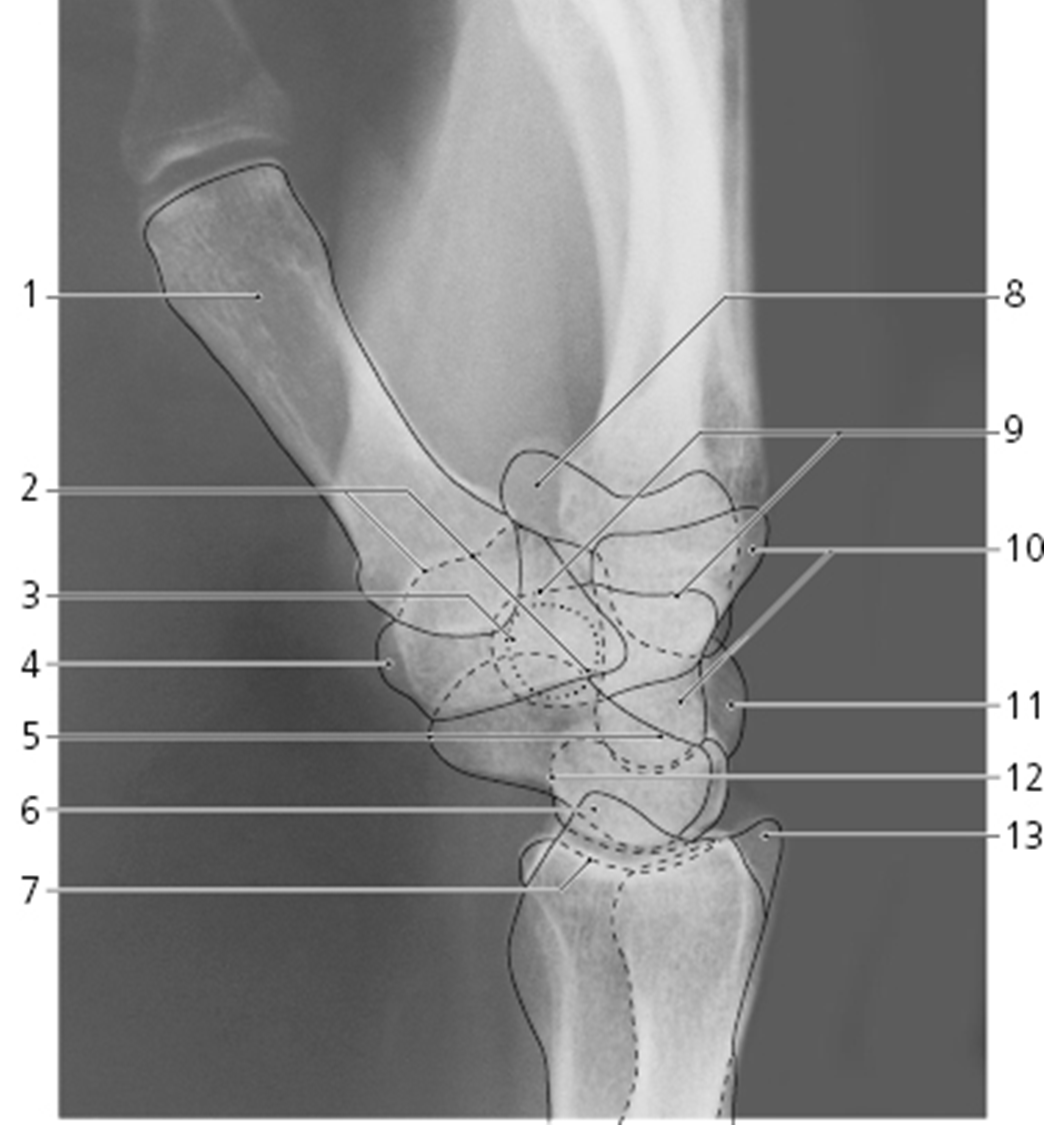

What is 13

what view is this?

lateral wrist